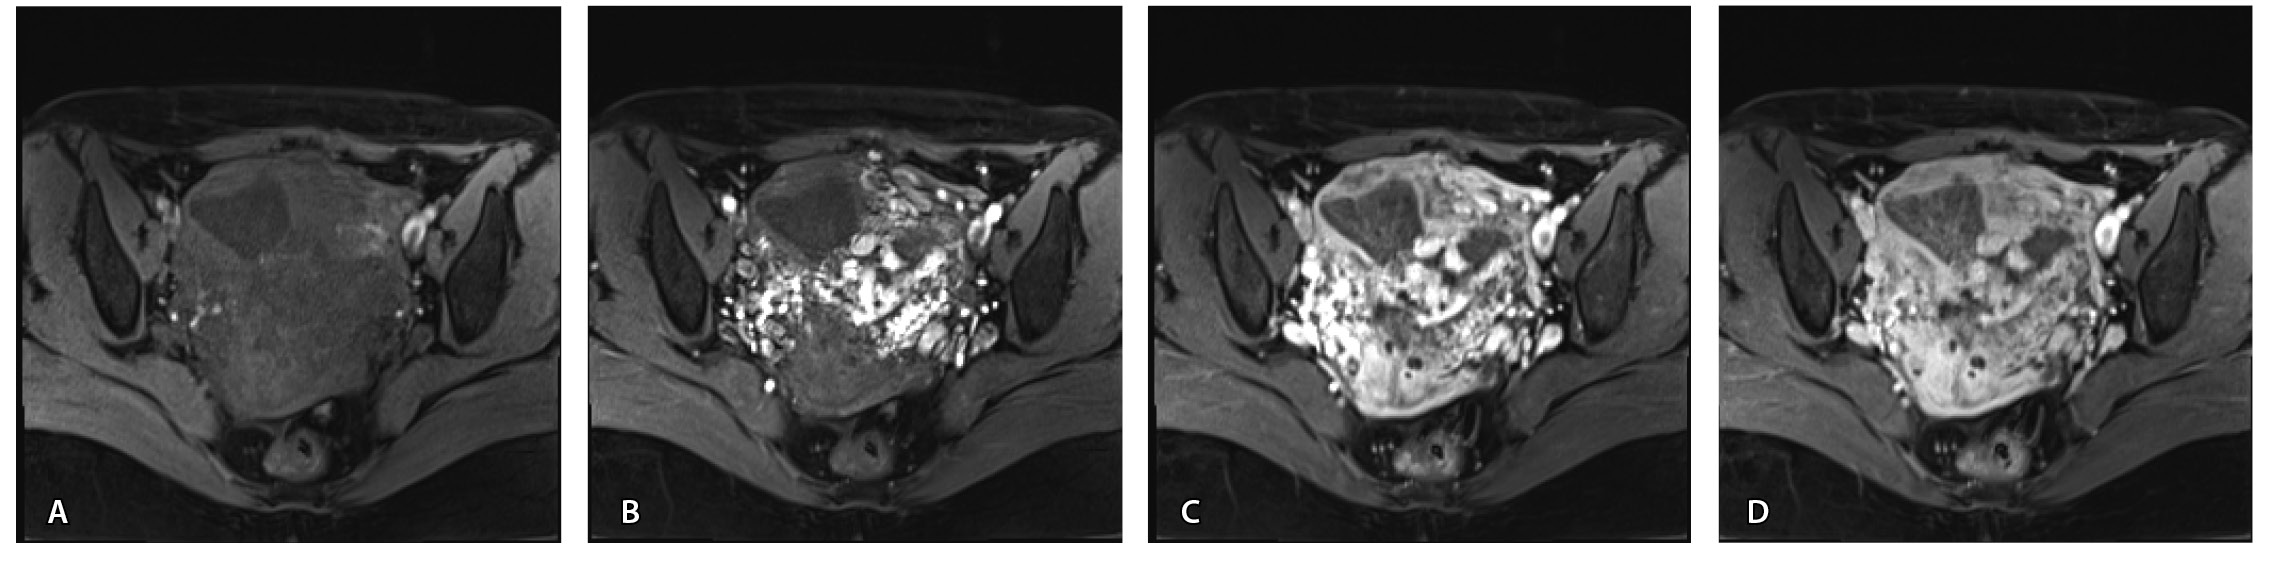

По наружной поверхности нижнего маточного сегмента и в параметрии определяется наличие полнокровной сосудистой сети с артериовенозными анастомозами. При контрастировании визуализируются фрагментарные участки гиперваскулярного накопления контраста вышеописанным образованием в рубцовой нише, а также определяется наличие артериовенозной сосудистой мальформации (рис. 2).

Рис. 2. Магнитно-резонансная томограмма, динамическое контрастное усиление в режиме Т1-взвешенного изображения FS. До контраста (А), в раннюю артериальную фазу (Б), паренхиматозную фазу (В), выделительную фазу (Г) определяются многочисленные патологические сосуды, зоны неоангиогенеза, сосудистые шунты как в стенке матки, так и в параметрии по типу артериовенозной мальформации